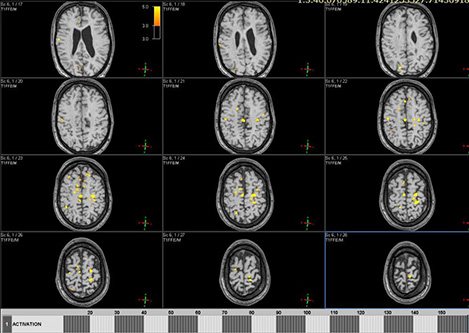

Цель: Апробация и внедрение в клиническую практику современных методик фМРТ и DTI для оценки структурных и функциональных изменений при нарушениях движения у детей. Описание проекта: Для Детского Церебрального Паралича характерно наличие незначительных структурных повреждений [1], при этом неясна их связь с нарушениями двигательных функций. фМРТ позволяет выявить зоны активации мозга при выполнении движений и оценить сложность выполнения задания по объему зон активации (Рис 1). МР-трактография позволяет исследовать структуру и диффузионные характеристики проводящих путей мозга (Рис 2). МР-волюметрия также позволяет оценить объем основных структур мозга и выявить аномалии развития, кортикальные дисплазии и патологии белого вещества мозга (Рис 3.). Результаты: Проведена клиническая апробация предложенных методик. Результаты представлены на медицинских неврологических конгрессах.